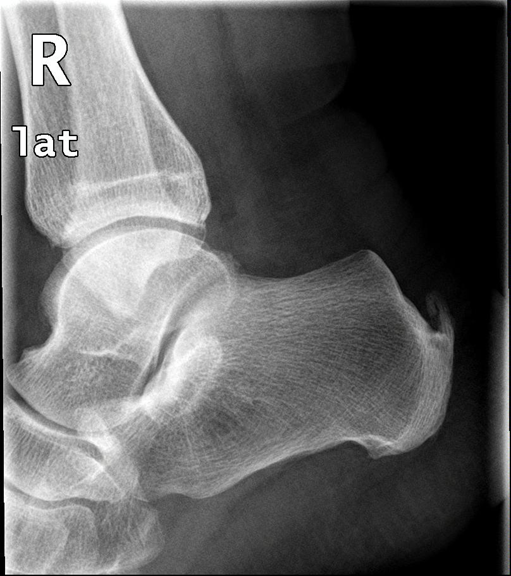

Πρόκειται για πάθηση που αναπτύσσεται στην κατάφυση του αχιλλείου τένοντα στο πίσω μέρος της πτέρνας. Η περιοχή είναι συνήθως ιδιαίτερα επώδυνη και διογκωμένη λόγω υπερόστωσης (οστικής υπερτροφίας) στην κατάφυση του αχιλλείου. Τα ενοχλήματα μπορεί να συνδυάζονται με πόνο στην περιοχή της πελματιαίας απονεύρωσης. Η πάθηση συχνά συνοδεύεται από τενοντίτιδα του αχιλλείου που καθιστά την θεραπευτική προσέγγιση δυσκολότερη.